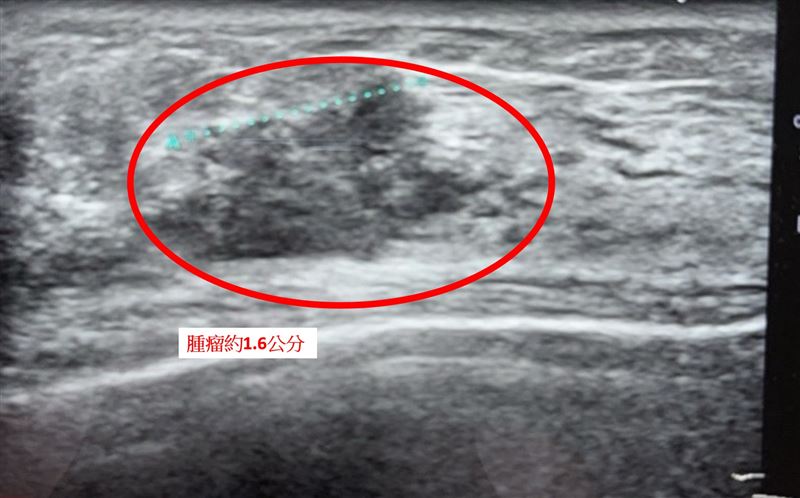

古君平表示,「多發性乳癌」指的是在同一側乳房中出現兩處以上、甚至分布於不同象限的腫瘤病灶。以該案例影像檢查顯示,患者右邊乳房至少可見三處病灶,最大約1.6公分,最小約0.6公分。由於多發性腫瘤可能在影像未顯現的區域仍存在潛在癌細胞,臨床上通常建議進行乳房全切除,以降低殘留與復發風險。